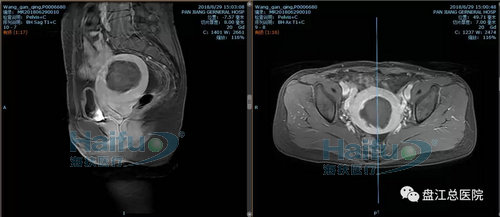

我院病例2:患者王XX,46歲,子宮腺肌癥患者。

因“發現盆腔包塊10+年,繼發性痛經2+年”入院。于2018年6月28日行高強度聚焦超聲消融治療(HIFU)。

治療經過:給予鎮靜鎮痛藥物后開始輻,患者訴稍有骶尾部及治療區脹痛不適,余未訴有不適,安靜休息配合治療。總治療時間25min。

術前磁共振增強橫斷位及矢狀位,見病灶內明顯強化

術后磁共振增強,見病灶內無明顯強化,病灶發生凝固性壞死